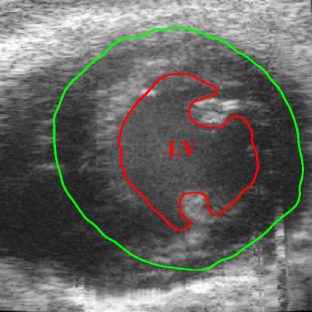

Left Ventricle Segmentation Using Model Fitting and Active Surfaces

A method to perform 4D (3D over time) seg mentation of the left ventricle of a mouse heart using a set of B mode cine slices acquired in vivo from a series of short axis scans is described. We incorporate previ ously suggested methods such as temporal propagation, the gradient vector flow active surface, superquadric models, etc. into our proposed 4D segmentation of the left ventricle. The contributions of this paper are incor poration of a novel despeckling method and the use of locally fitted superellipsoid models to provide a better initialization for the active surface segmentation algorithm. Average distances of the improved surface segmentation to a manually segmented surface through out the entire cardiac cycle and cross-sectional contours are provided to demonstrate the improvements pro duced by the proposed 4D segmentation.